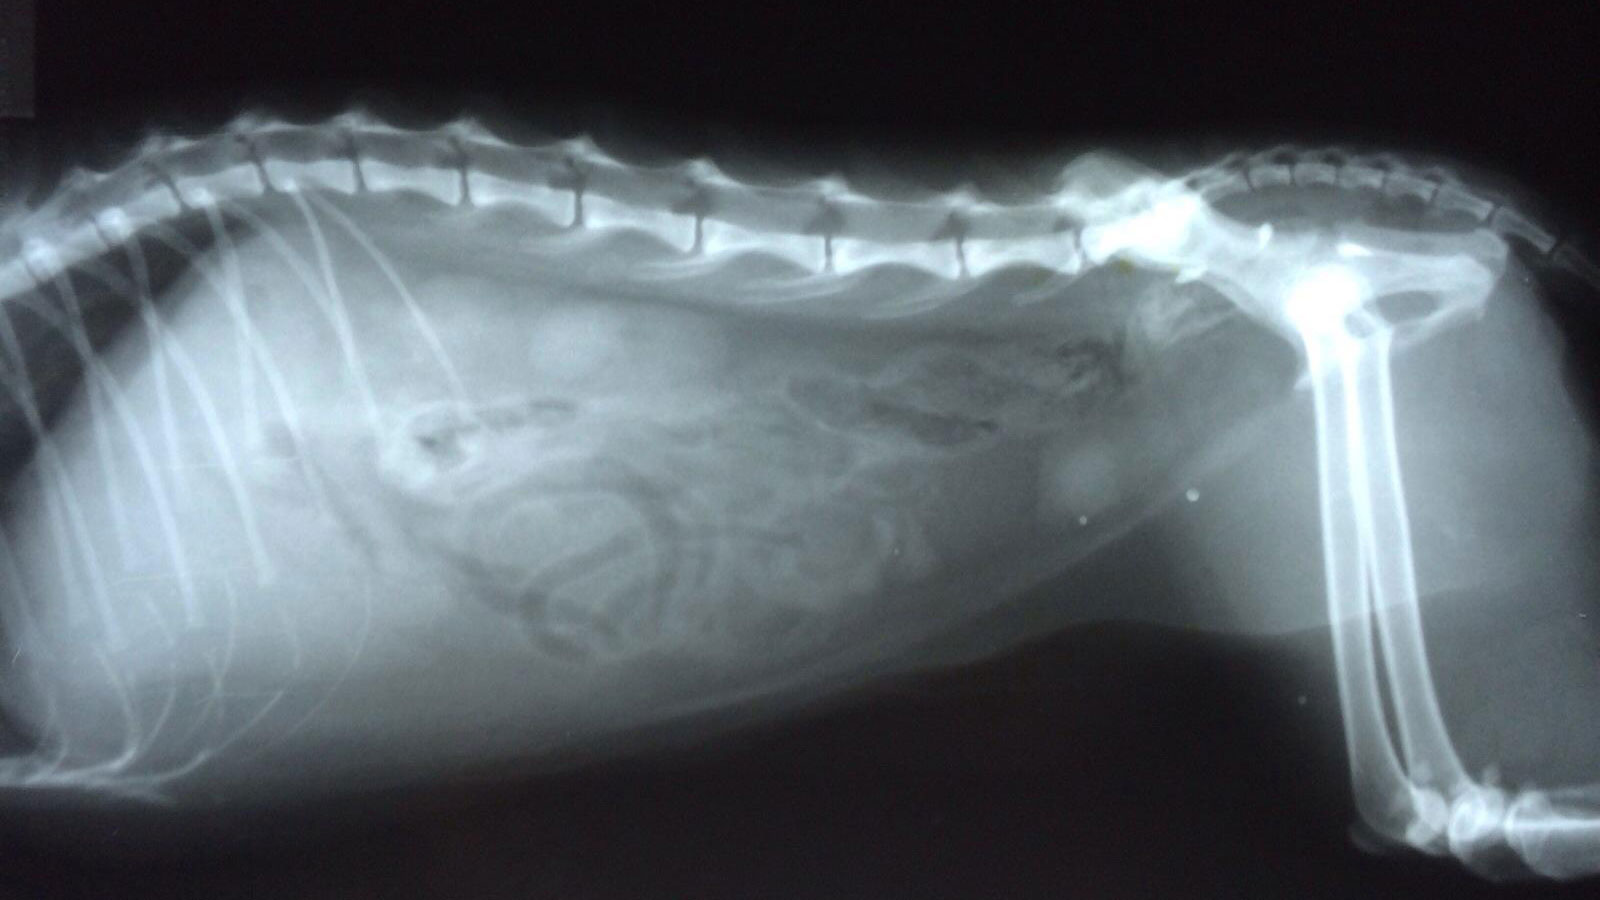

三、临床诊断

★触诊

出现排尿困难、尿频等症状时要触诊检查腹部,若触摸到腹部平坦,则说明无尿或者少尿,可能是尿道受到刺激的原因;若触摸到膀胱充盈,腹壁紧张,则说明尿路发生阻塞,应进一步检查。注意:若腹部膨大,切忌在触摸过程中太过用力,以免充盈肿胀的膀胱因外力的作用而破裂。

★B超检查

对膀胱充盈的猫可直接进行B超检査,正常的膀胱超声图像呈1个无回声的液性暗区,若有结石,图像上会出现较明亮的强回声光点或团块,伴有明显的声影。结石会随着动物体位的变化而变化,小的结石或结晶等会在膀胱中上下沉浮,通过改变动物的体位,观察强光点随着体位改变的变化,借此方法可以排除肿瘤等其他原因引起的强回声反射。炎症情况下或结石长期刺激,有时可见增厚的膀胱壁。